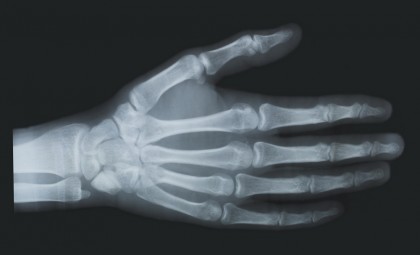

Îmbătrânirea scheletică: factorii epigenetici influențează pierderea osoasă

Celulele din măduva osoasă, cunoscute sub numele de celule stem mezenchimale, servesc drept elemente constitutive ale țesuturilor scheletice ale corpului. Atunci când aceste celule stem se dezvoltă în țesuturi osoase sau grase, sunt controlate parțial de factori epigenetici, molecule care reglează genele. Echipa de cercetători condusă de Cun-Yu Wang a demonstrat că atunci când factorul epigenetic KDM4B este absent din celulele stem mezenchimale, aceste celule sunt mult mai predispuse să se diferențieze în celule grase, rezultând un dezechilibru nesănătos care exacerbează îmbătrânirea scheletului și duce la oase fragile și fracturi în timp.

În urma studiilor de laborator, cercetătorii au descoperit că îndepărtarea enzimei KDM4B a obligat celulele stem mezenchimale să creeze mai multe grăsimi în loc de țesut osos, ducând la pierderea osoasă în timp, care imită îmbătrânirea scheletului. Echipa a descoperit, de asemenea, că senescența, care duce la îmbătrânirea naturală a scheletului, a fost caracterizată de o pierdere a KDM4B.

În plus față de vârstă, se crede că alți factori de mediu reduc calitatea oaselor și exacerbează pierderea osoasă, inclusiv o dietă bogată în grăsimi. Echipa a demonstrat că pierderea KDM4B a favorizat în mod semnificativ pierderea osoasă și acumularea de grăsime de măduvă la șoarecii plasați pe o dietă bogată în grăsimi. În cele din urmă, echipa a arătat că hormonul paratiroidian, un medicament anabolic aprobat de Administrația pentru Alimente și Medicamente pentru tratamentul pierderii osoase legate de îmbătrânire ajută la menținerea bazinului de celule stem mezenchimale la șoarecii în vârstă într-o manieră dependentă de KDM4B.